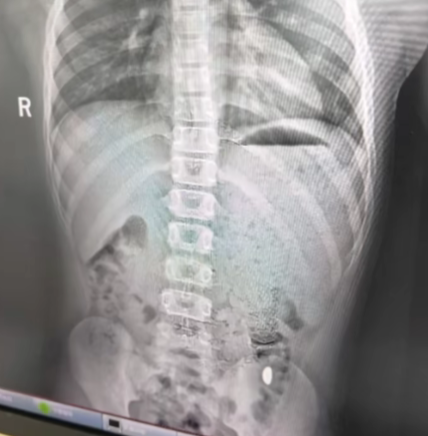

After five days of monitoring without results, Ms Ji finally took her son to Kunshan Fifth People’s Hospital on 26 Oct, where doctors found a foreign object in his stomach.

Fortunately, he showed no symptoms of pain or vomiting.

Later that day, the gold bean was successfully retrieved, though it was unclear whether it was expelled naturally or removed by doctors.